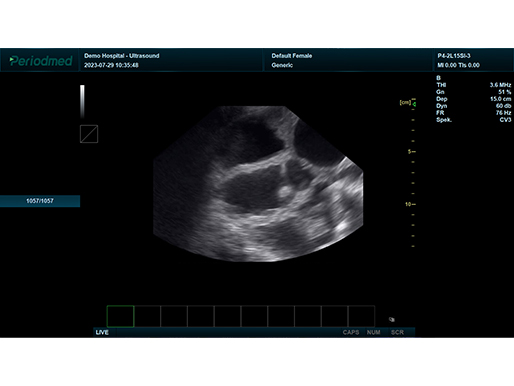

B模式 子宫 猪

B模式 子宫 猪

凸阵探头-B模式-子宫 猪

凸阵探头-B模式-子宫 猪